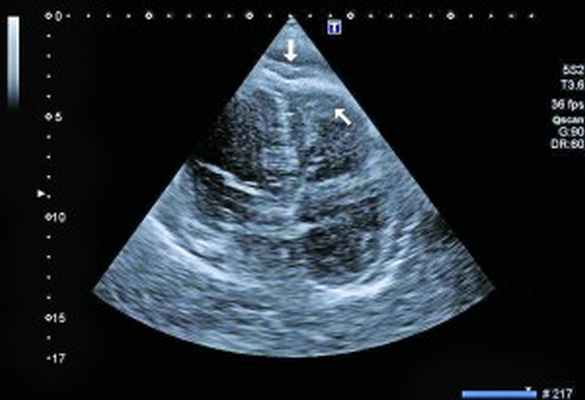

Рис. 3. Тромб у верхушки ПЖ, уплотнение между листками перикарда в области верхушки (четырехкамерная позиция сердца)

ЭхоКГ: Патологические изменения миокарда ПЖ с утолщением стенок до 18 мм. Диффузный гипокинез стенок ЛЖ с дискинезом верхушки – ФВ 44%. В области верхушки ПЖ – наслоения между листками перикарда. Небольшое количество жидкости в полости перикарда – по ЗСЛЖ до 5 мм. Таким образом, в динамике на ЭхоКГ наблюдалось снижение сократительной функции ЛЖ на фоне его гипертрофии и, несмотря на проведенную высокодозовую терапию гормонами, не уменьшилась гипертрофия ПЖ.